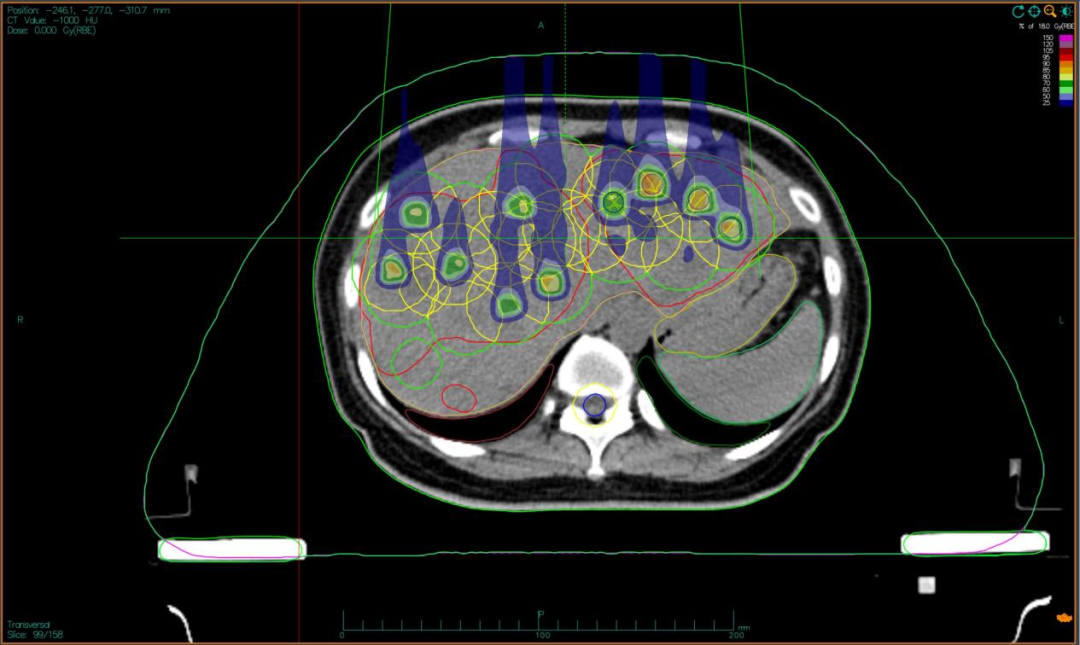

二,采用“晶格放疗”先进布野技术,在巨大肝肿瘤内部精准布设能量“棋盘格”,在高效杀伤肿瘤细胞的同时,为残存正常肝组织与关键脉管留存生存空间;